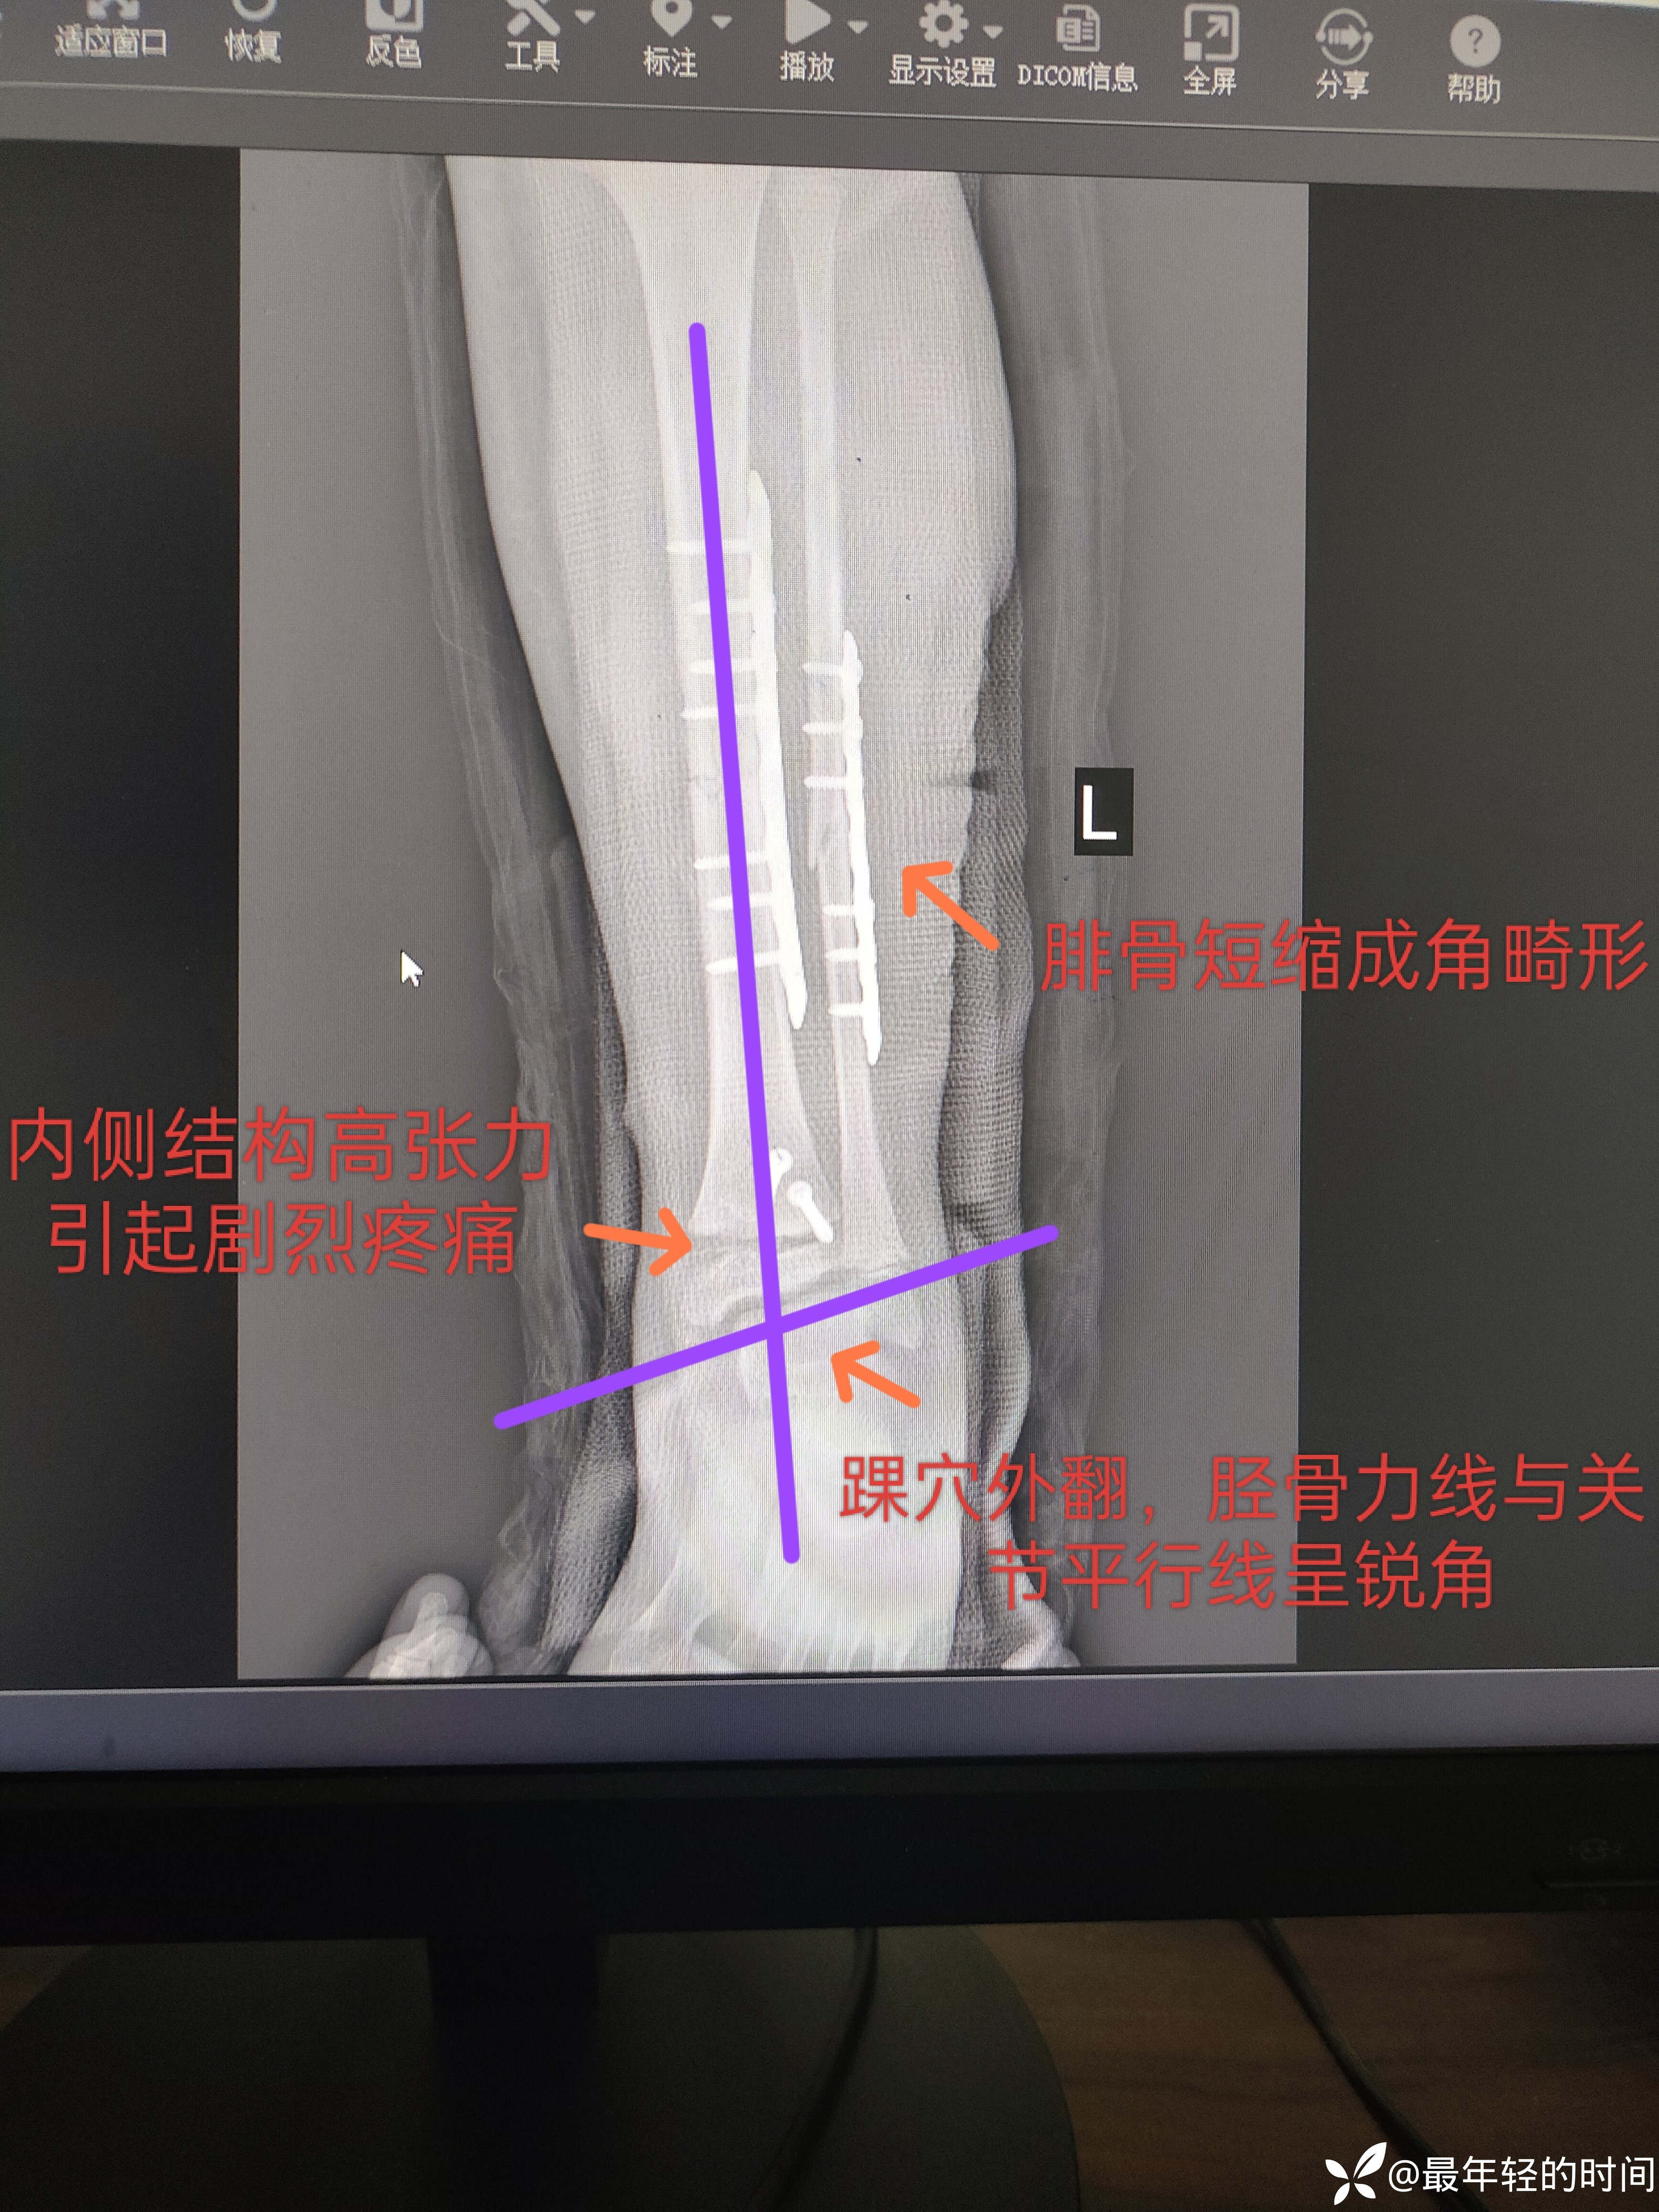

消肿后行切开复位钢板螺钉内固定。术后患儿足踝部及足背部疼痛剧烈,目前术后一周,疼痛症状任未有效缓解。术后片如下:

手术方式我本就不赞同,我更倾向于弹性髓内钉固定胫腓骨骨干,解剖复位骨骺损伤螺钉固定后踝(本例手术是同科室另外一组人做的)。各位老师看看术后片有没有发现问题所在呢?我也简单的分析了一下。虽然科主任听了我提出的问题表示的很不屑,但是我还是坚信自己。这里想请教各位儿骨的老师们,这个手术对该患儿踝关节的功能会有什么样的影响?如果影响比较大,现在最好的处理方式是什么?

懂得人一看就懂,其实后踝和骨骺的复位也不是太理想的。踝穴外翻,踝关节承重不平衡。个人觉得对患者功能影响应该是挺大的。我也不想诋毁同行,只想请教一下各位老师,像这种情况会不会在生长发育的过程中得以纠正?如果不能,现在最好的补救措施是什么?